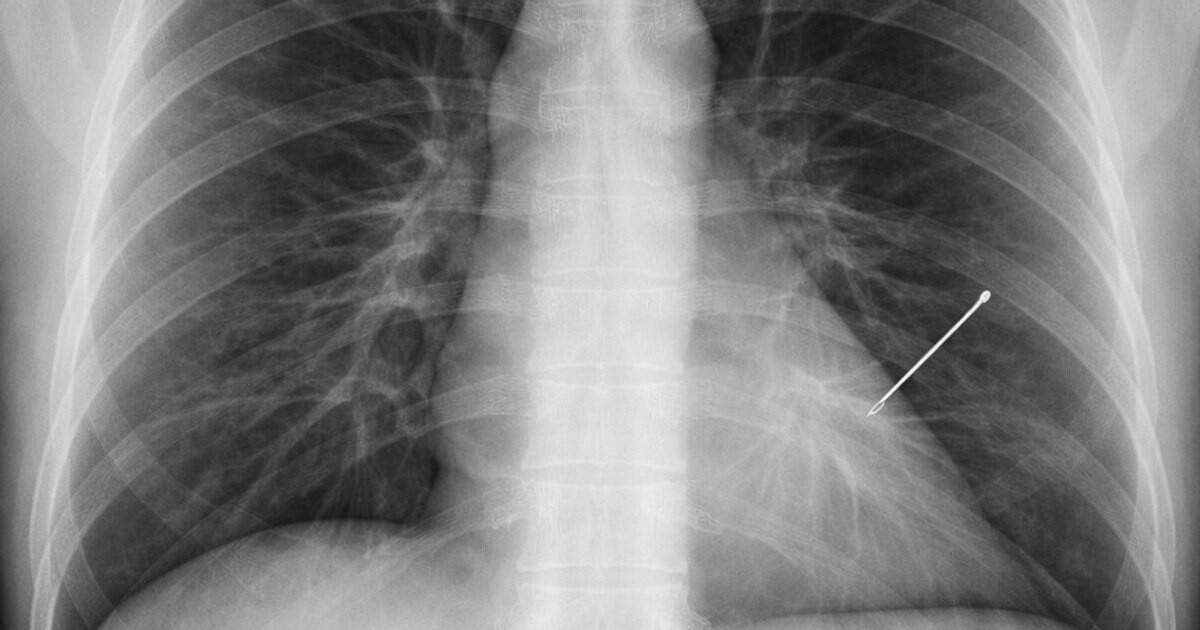

Un caz medical neobișnuit a fost descoperit întâmplător la o femeie de 55 de ani, în timpul unui control de rutină: o radiografie a arătat prezența unui ac de cusut în plămânul stâng, care ar fi rămas în organism, timp de aproape 30 de ani.

„Radiografia care m-a lăsat fără cuvinte după 20 de ani de experiență. În radiologie vezi de toate. După 20 de ani, crezi că nimic nu te mai poate surprinde. Și totuși. O pacientă de ~55 de ani vine pentru o radiografie pulmonară de rutină. Control periodic, nimic special. Pun radiografia pe ecran. Și îngheț. În plămânul stâng, clar vizibil, un ac de cusut”, a relatat medical.

Radiologul spune că acul ar fi rămas în organism fără să provoace probleme majore: „30 de ani. Acul migrase și stătea cuminte în plămân fără să facă probleme.”